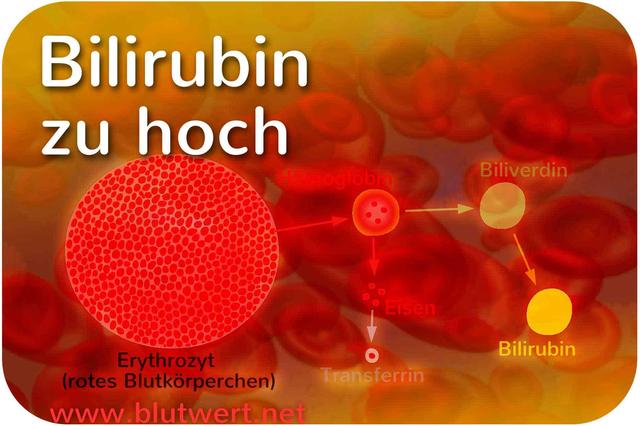

Bilirubin, ein gelbes Pigment, das bei der Zersetzung roter Blutkörperchen entsteht, kann bei Erwachsenen gefährlich werden. Doch ab welchem Wert sollte man besorgt sein? In diesem Artikel erfahren Sie alles Wichtige über die potenziellen Gefahren von Bilirubin im Erwachsenenalter und wann ein erhöhter Bilirubinwert auf eine ernsthafte Erkrankung hinweisen kann. Bleiben Sie informiert und schützen Sie Ihre Gesundheit!

Eine erhöhte Bilirubinkonzentration im Blut kann zu Gelbsucht oder Ikterus führen. Bei Erwachsenen tritt eine erkennbare Gelbsucht auf, wenn der Bilirubinspiegel mehr als 2,5 mg/dl beträgt. Dieses Symptom ist ein Anzeichen für eine mögliche gesundheitliche Störung.

Bei Erwachsenen wird eine Bilirubinkonzentration von mehr als 2,5 mg/dl als gefährlich angesehen. Ein erhöhter Bilirubinspiegel kann darauf hinweisen, dass der Farbstoff in der Lederhaut des Auges und in der Haut eingelagert wird. In einigen Fällen kann dies auf eine Schädigung der Leber oder andere ernsthafte Erkrankungen hinweisen.

Bei Erwachsenen besteht ab einem Bilirubinspiegel von mehr als 2,5 mg/dl ein erhöhtes Risiko für eine Gelbsucht oder Ikterus. Dies bedeutet, dass der Gallenfarbstoff Bilirubin in der Lederhaut des Auges und in der Haut eingelagert wird. Eine erkennbare Gelbsucht tritt normalerweise erst auf, wenn der Bilirubinspiegel diesen Wert überschreitet.

Die Bestimmung der Bilirubinwerte im Blutserum kann wichtige Informationen über den Zustand des Körpers liefern. Ein erhöhter Bilirubinspiegel kann auf verschiedene Erkrankungen hinweisen. Normalerweise sollte der Gesamtgehalt des Bilirubins im Serum unter 21 µmol/l liegen.

2. Unterscheidung der Bilirubinfraktionen

Bei der Bestimmung des Bilirubinwertes werden verschiedene Fraktionen unterschieden. Das indirekte Bilirubin ist die unkonjugierte, wasserunlösliche Form, die an das Protein Albumin gebunden ist. Das direkte Bilirubin hingegen ist die konjugierte, wasserlösliche Form. Zusätzlich gibt es noch das Delta-Bilirubin, welches eine kovalente Bindung mit Albumin eingeht.